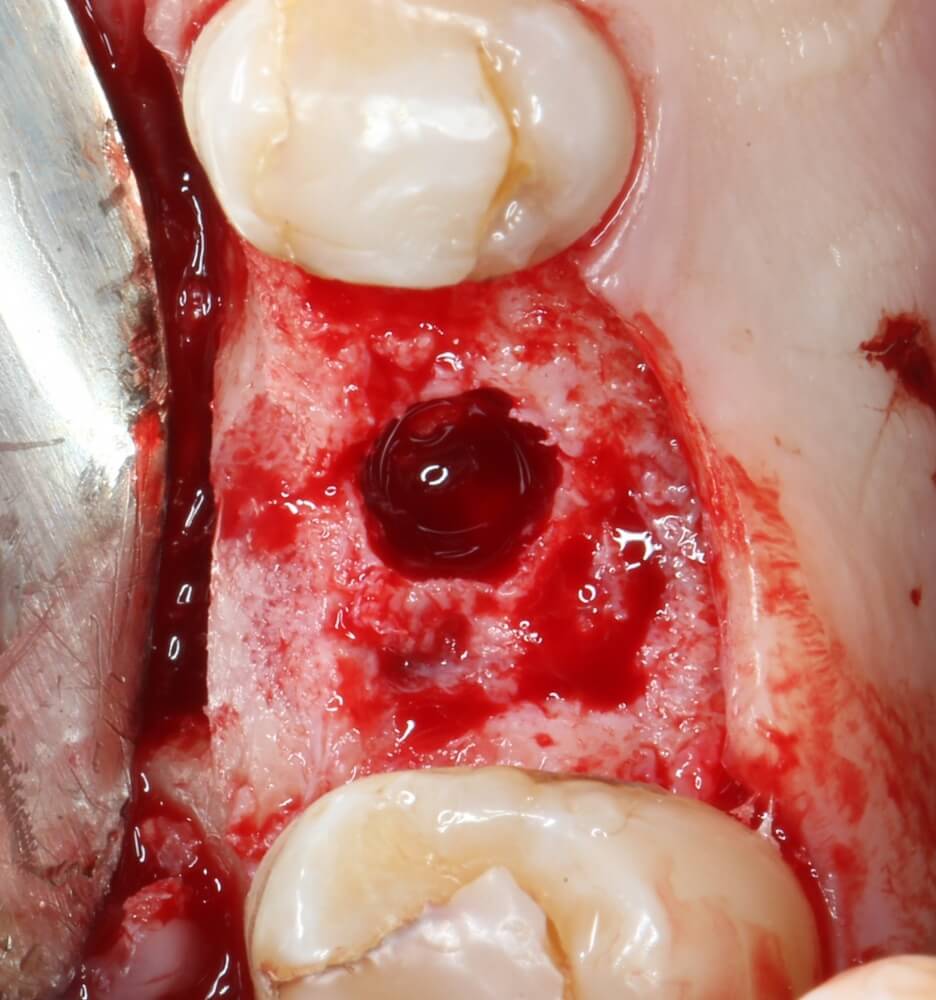

Начинаем подготовку лунки под имплантат

Первым инструментом из хирургического набора является шариковый бор. Он нужен для того, чтобы разметить положение имплантата:

Многие доктора (и некоторые производители имплантационных систем) заменяют шариковый бор в хирургическом наборе на фрезу Линдеманна или пику. На самом деле, шарик намного удобнее, поскольку не заклинивает в плотной кости, может работать любой поверхностью, а его основная функция — поставить точку на поверхности альвеолярного гребня, через которую потом пройдёт ось имплантата. Так что совсем уж углубляться шариком в кость не нужно. Тем более, не стоит проходить им всю глубину будущей лунки. Поставили точку — и всё на этом.